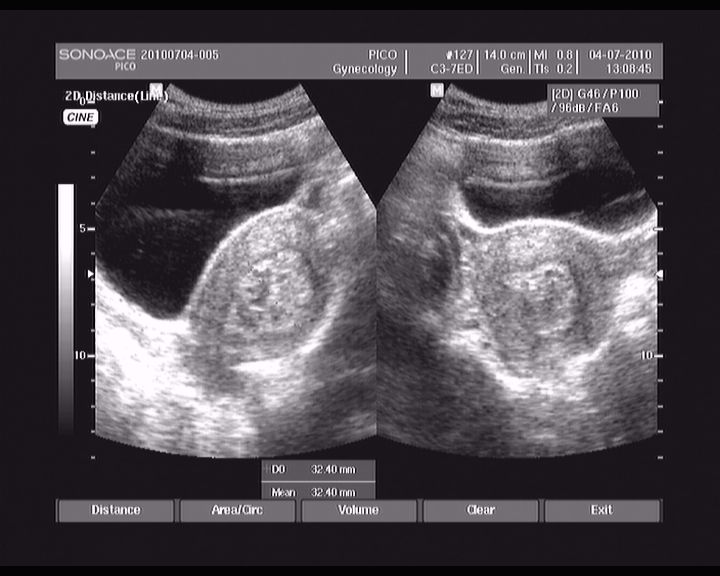

abrasio 01.07.2010

11.jpg